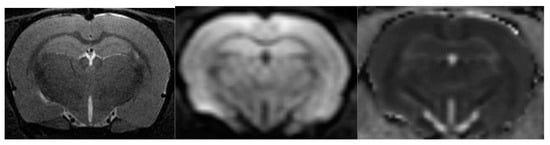

4.5. Diffusion-Weighted Magnetic Resonance Imaging

As with MRA, DWI was performed in one scan session with two other MRI techniques [58]. To obtain diffusion-weighted tomograms, a three-dimensional echo-planar pulse sequence was used with the following parameters: TE = 15.4 ms; TR = 2000 ms; the amount of excitation is 1, and the isotropic voxel size is 200 µm. The data were obtained using a multi-pass acquisition with five directions and three repetitions for b = 0, 100, 200, 500, 1000 s/mm2. DWI data processing with measured diffusion coefficient (ADC) estimation was performed using ParaVision 5.1, Image Sequence Analysis Tool, dtraceb function from Bruker sequence analysis library to generate average ADC for each ROI based on the equation: ADC = ln (S0/Sn)/bn, where S0 is an intensity of the T2-weighted image (b = 0), and Sn is an intensity of the diffusion-weighted image with bn as the decay factor of the diffusion gradient. This data processing step resulted in a parametric map of the numerical values of the measured diffusion coefficient. Eight brain slices with calculated ADCs were obtained; they anatomically corresponded to T2-weighted images in the Bregma range: from 1.2 mm to −3.4 mm). Please see Figure 16 for corresponding brain images.

To correct for apparent translational motion caused by frequency drift and gradient diffusion, all slices were aligned using T2-weighted images and by strict registration orientation. The measured diffusion coefficient was assessed in the hippocampus (HPF).

Figure 16. From left to right are images of T2-WI, DWI, ADC.